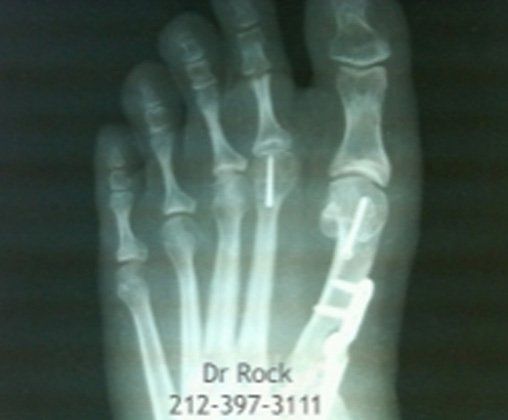

Get Beautiful, Pain-Free Feet

Take a look at our x-ray pictures of our recent footwork and see how your feet can benefit.

Whether you want to improve the look of your feet or need to relieve pain,

you can find out the best option for you with our FREE phone consultation.